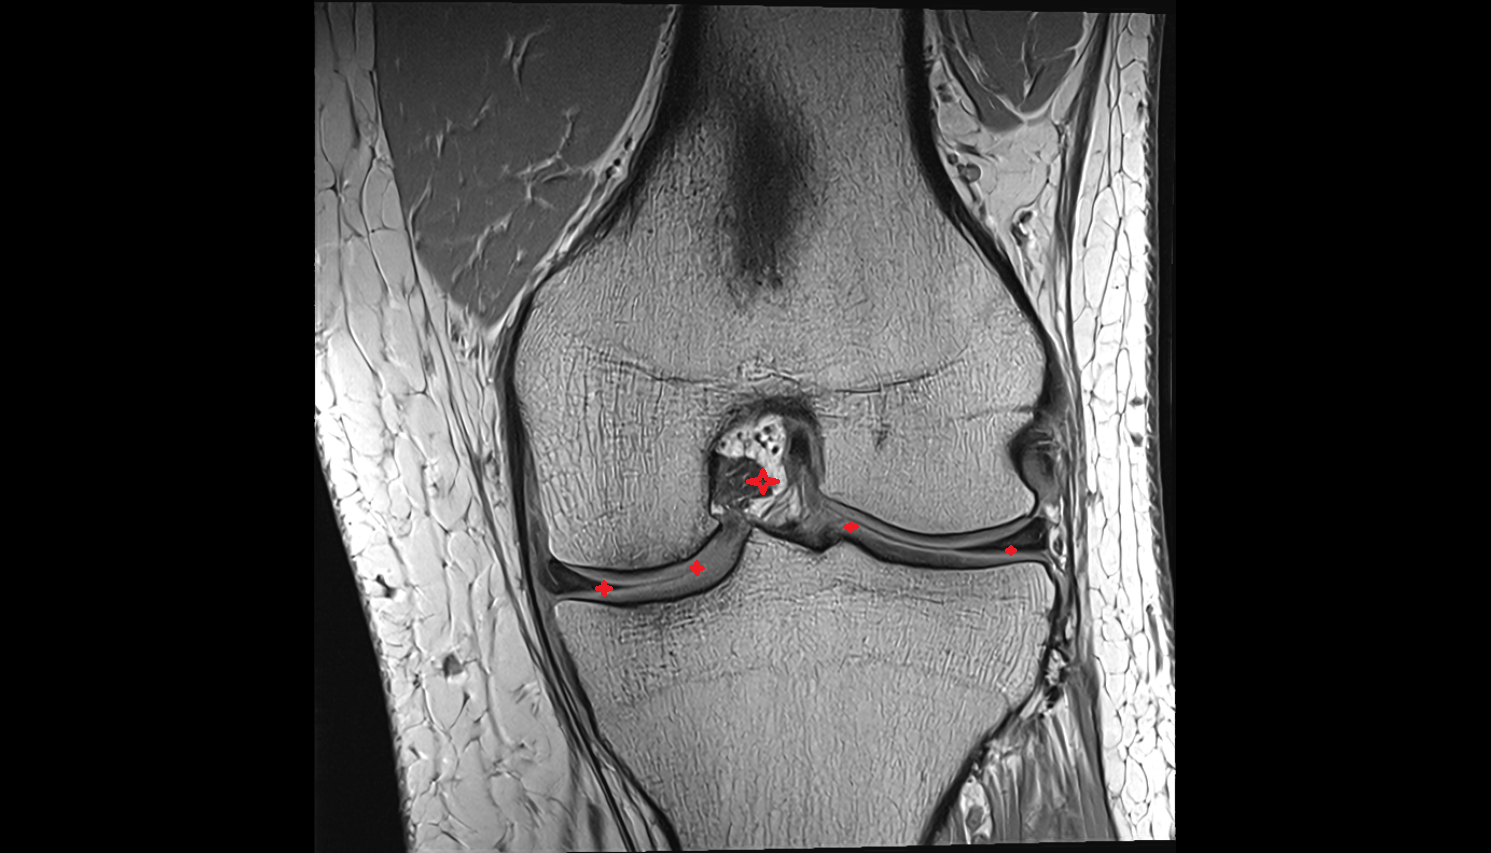

- Medial meniscus

- Lateral meniscus

- Anterior horn of medial meniscus

- Posterior horn of medial meniscus

- Body of medial meniscus

- Anterior root of medial meniscus

- Posterior root of medial meniscus

- Anterior horn of lateral meniscus

- Posterior horn of lateral meniscus

- Body of lateral meniscus

- Anterior root of lateral meniscus

- Posterior root of lateral meniscus